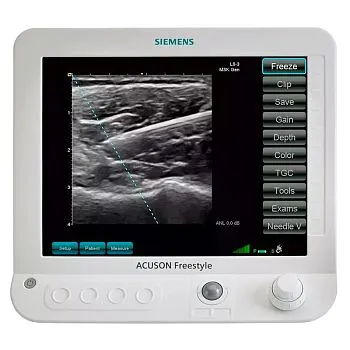

УЗИ аппарат Mindray M6 портативный

Клинические изображения